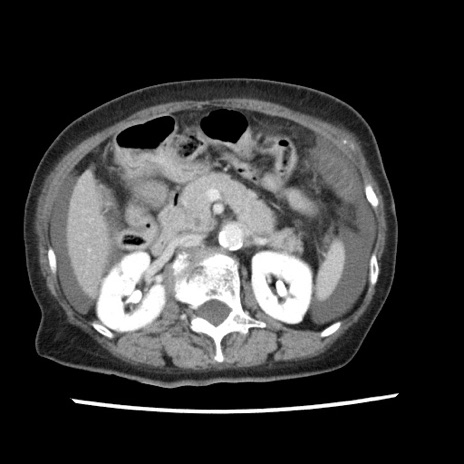

症例1(横断像)

【症例】80歳代女性

【主訴】腹痛

【現病歴】8時間前から腹痛あり来院。

【既往歴】糖尿病、脂質異常症、子宮体癌にて子宮全摘術

【身体所見】意識清明・会話良好だが腹痛で苦悶様、全腹部にわたって反跳痛と圧痛あり

【データ】WBC 13600、CRP 0.14、LDH 224、CK 90